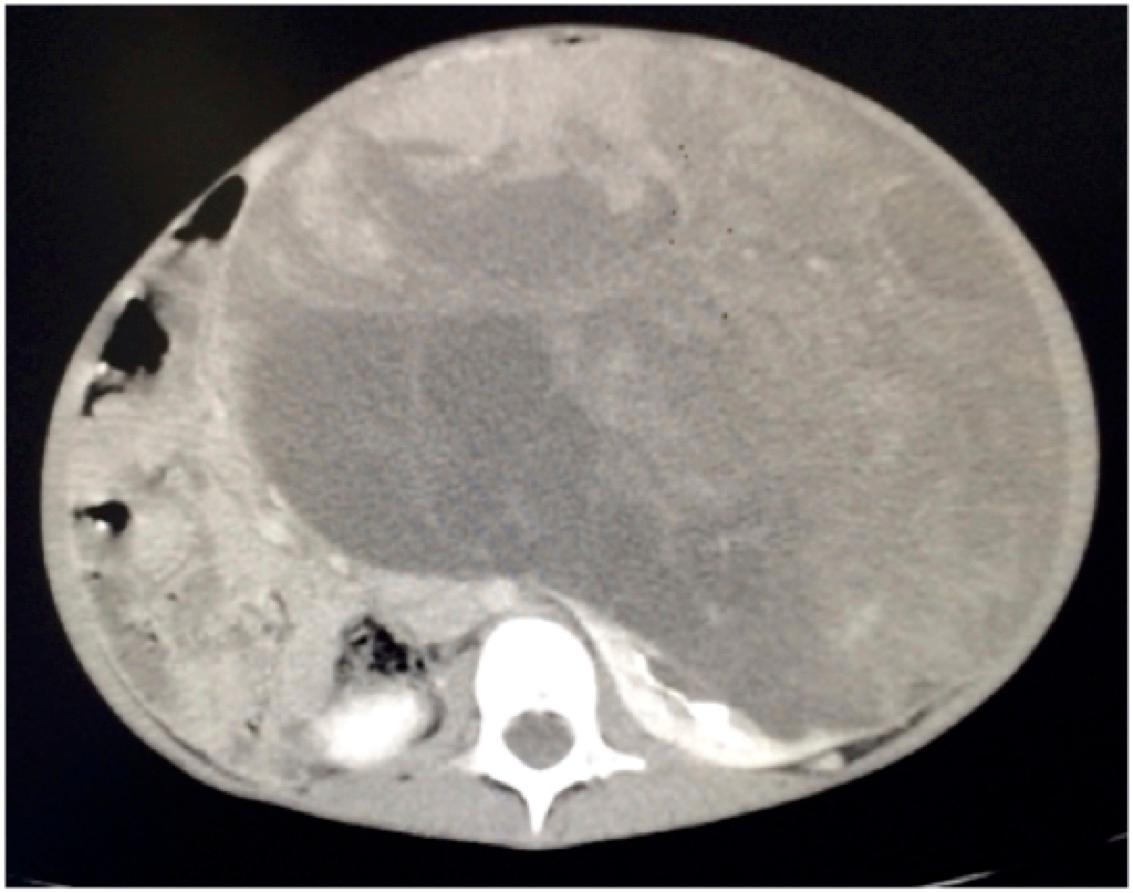

What is the best next step in this child’s management?

The next step in the management of this patient is:

The next best step in management of this child with bilateral renal masses is

Given the stage, the most appropriate initial treatment of this renal mass would be

The recommended next step for this patient with a presumed cystic renal tumor is